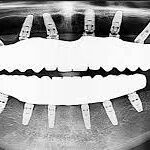

Before and After

SEE OUR RESULTS